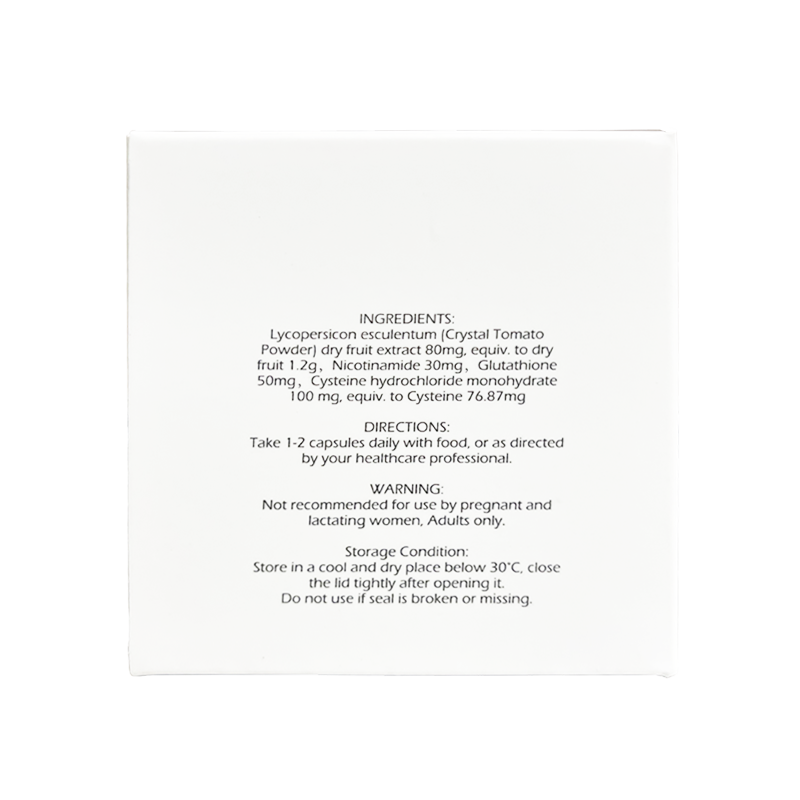

Each capsule delivers a clean and effective blend of Lycopersicon esculentum (Crystal Tomato Powder) dry fruit extract, Nicotinamide, Glutathione and Cysteine hydrochloride monohydrate to ensure both safety and reliable performance.

Each bottle contain: Lycopersicon esculentum (Crystal Tomato Powder) dry fruit extract,

Nicotinamide, Glutathione, Cysteine hydrochloride monohydrate

Take 1-2 capsules daily with food, or as directed by your healthcare professional.